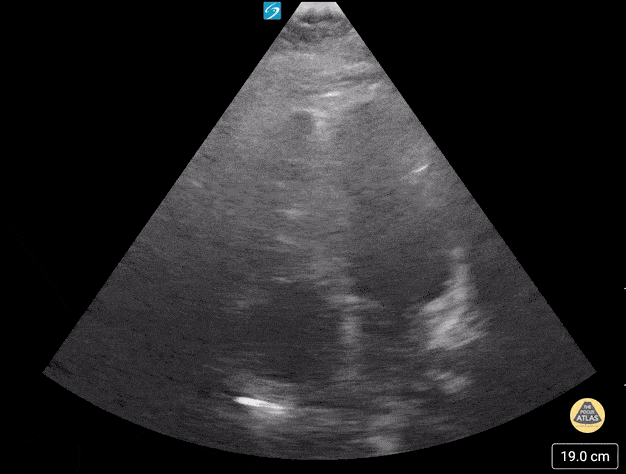

Teenager in ventricular tachycardia. Contributor: Peter Gutierrez, MD, FAAP, Emory University School of Medicine/Children's Healthcare of Atlanta, @pocuspete